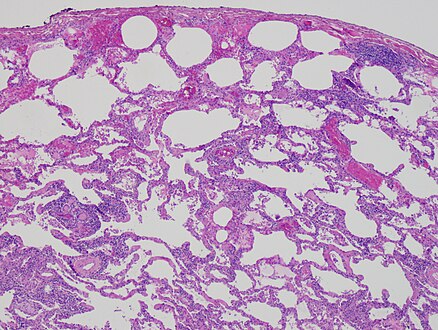

High magnification photomicrograph of a lung biopsy taken showing chronic hypersensitivity pneumonitis (H&E), showing mild thickening of the walls of the small air sacs by invasion of white blood cells. A multinucleated giant cell, seen within the walls of the air sacs to the right of the picture halfway down, is an important clue to the correct diagnosis.

Lung biopsies can be diagnostic in cases of chronic hypersensitivity pneumonitis, or may help to suggest the diagnosis and trigger or intensify the search for an allergen. The main feature of chronic hypersensitivity pneumonitis on lung biopsies is expansion of the interstitium by lymphocytes accompanied by an occasional multinucleated giant cell or loose granuloma.[20][21]

When fibrosis develops in chronic hypersensitivity pneumonitis, the differential diagnosis in lung biopsies includes the idiopathic interstitial pneumonias.[22] This group of diseases includes usual interstitial pneumonia, non-specific interstitial pneumonia and cryptogenic organizing pneumonia, among others.[20][21]

The prognosis of some idiopathic interstitial pneumonias, e.g. idiopathic usual interstitial pneumonia (i.e. idiopathic pulmonary fibrosis), are very poor and the treatments of little help. This contrasts the prognosis (and treatment) for hypersensitivity pneumonitis, which is generally fairly good if the allergen is identified and exposures to it significantly reduced or eliminated. Thus, a lung biopsy, in some cases, may make a decisive difference.